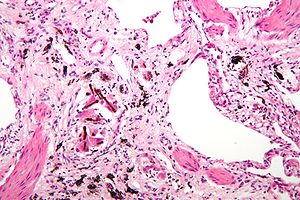

Asbestosis. H&E stain. | |

| LM | interstitial fibrosis (similar to usual interstitial pneumonia), ferruginous bodies (segmented twirling baton with long slender fibre within it) |

| LM DDx | usual interstitial pneumonia |

| Stains | Iron stain +ve (ferruginous bodies) |

- Interstitial fibrosis - similar to usual interstitial pneumonia (UIP).

- Ferruginous bodies - key feature.

- Segmented twirling baton with long slender fibre within.

- Black crystal-like appearance - may be confused with dirt on H&E.